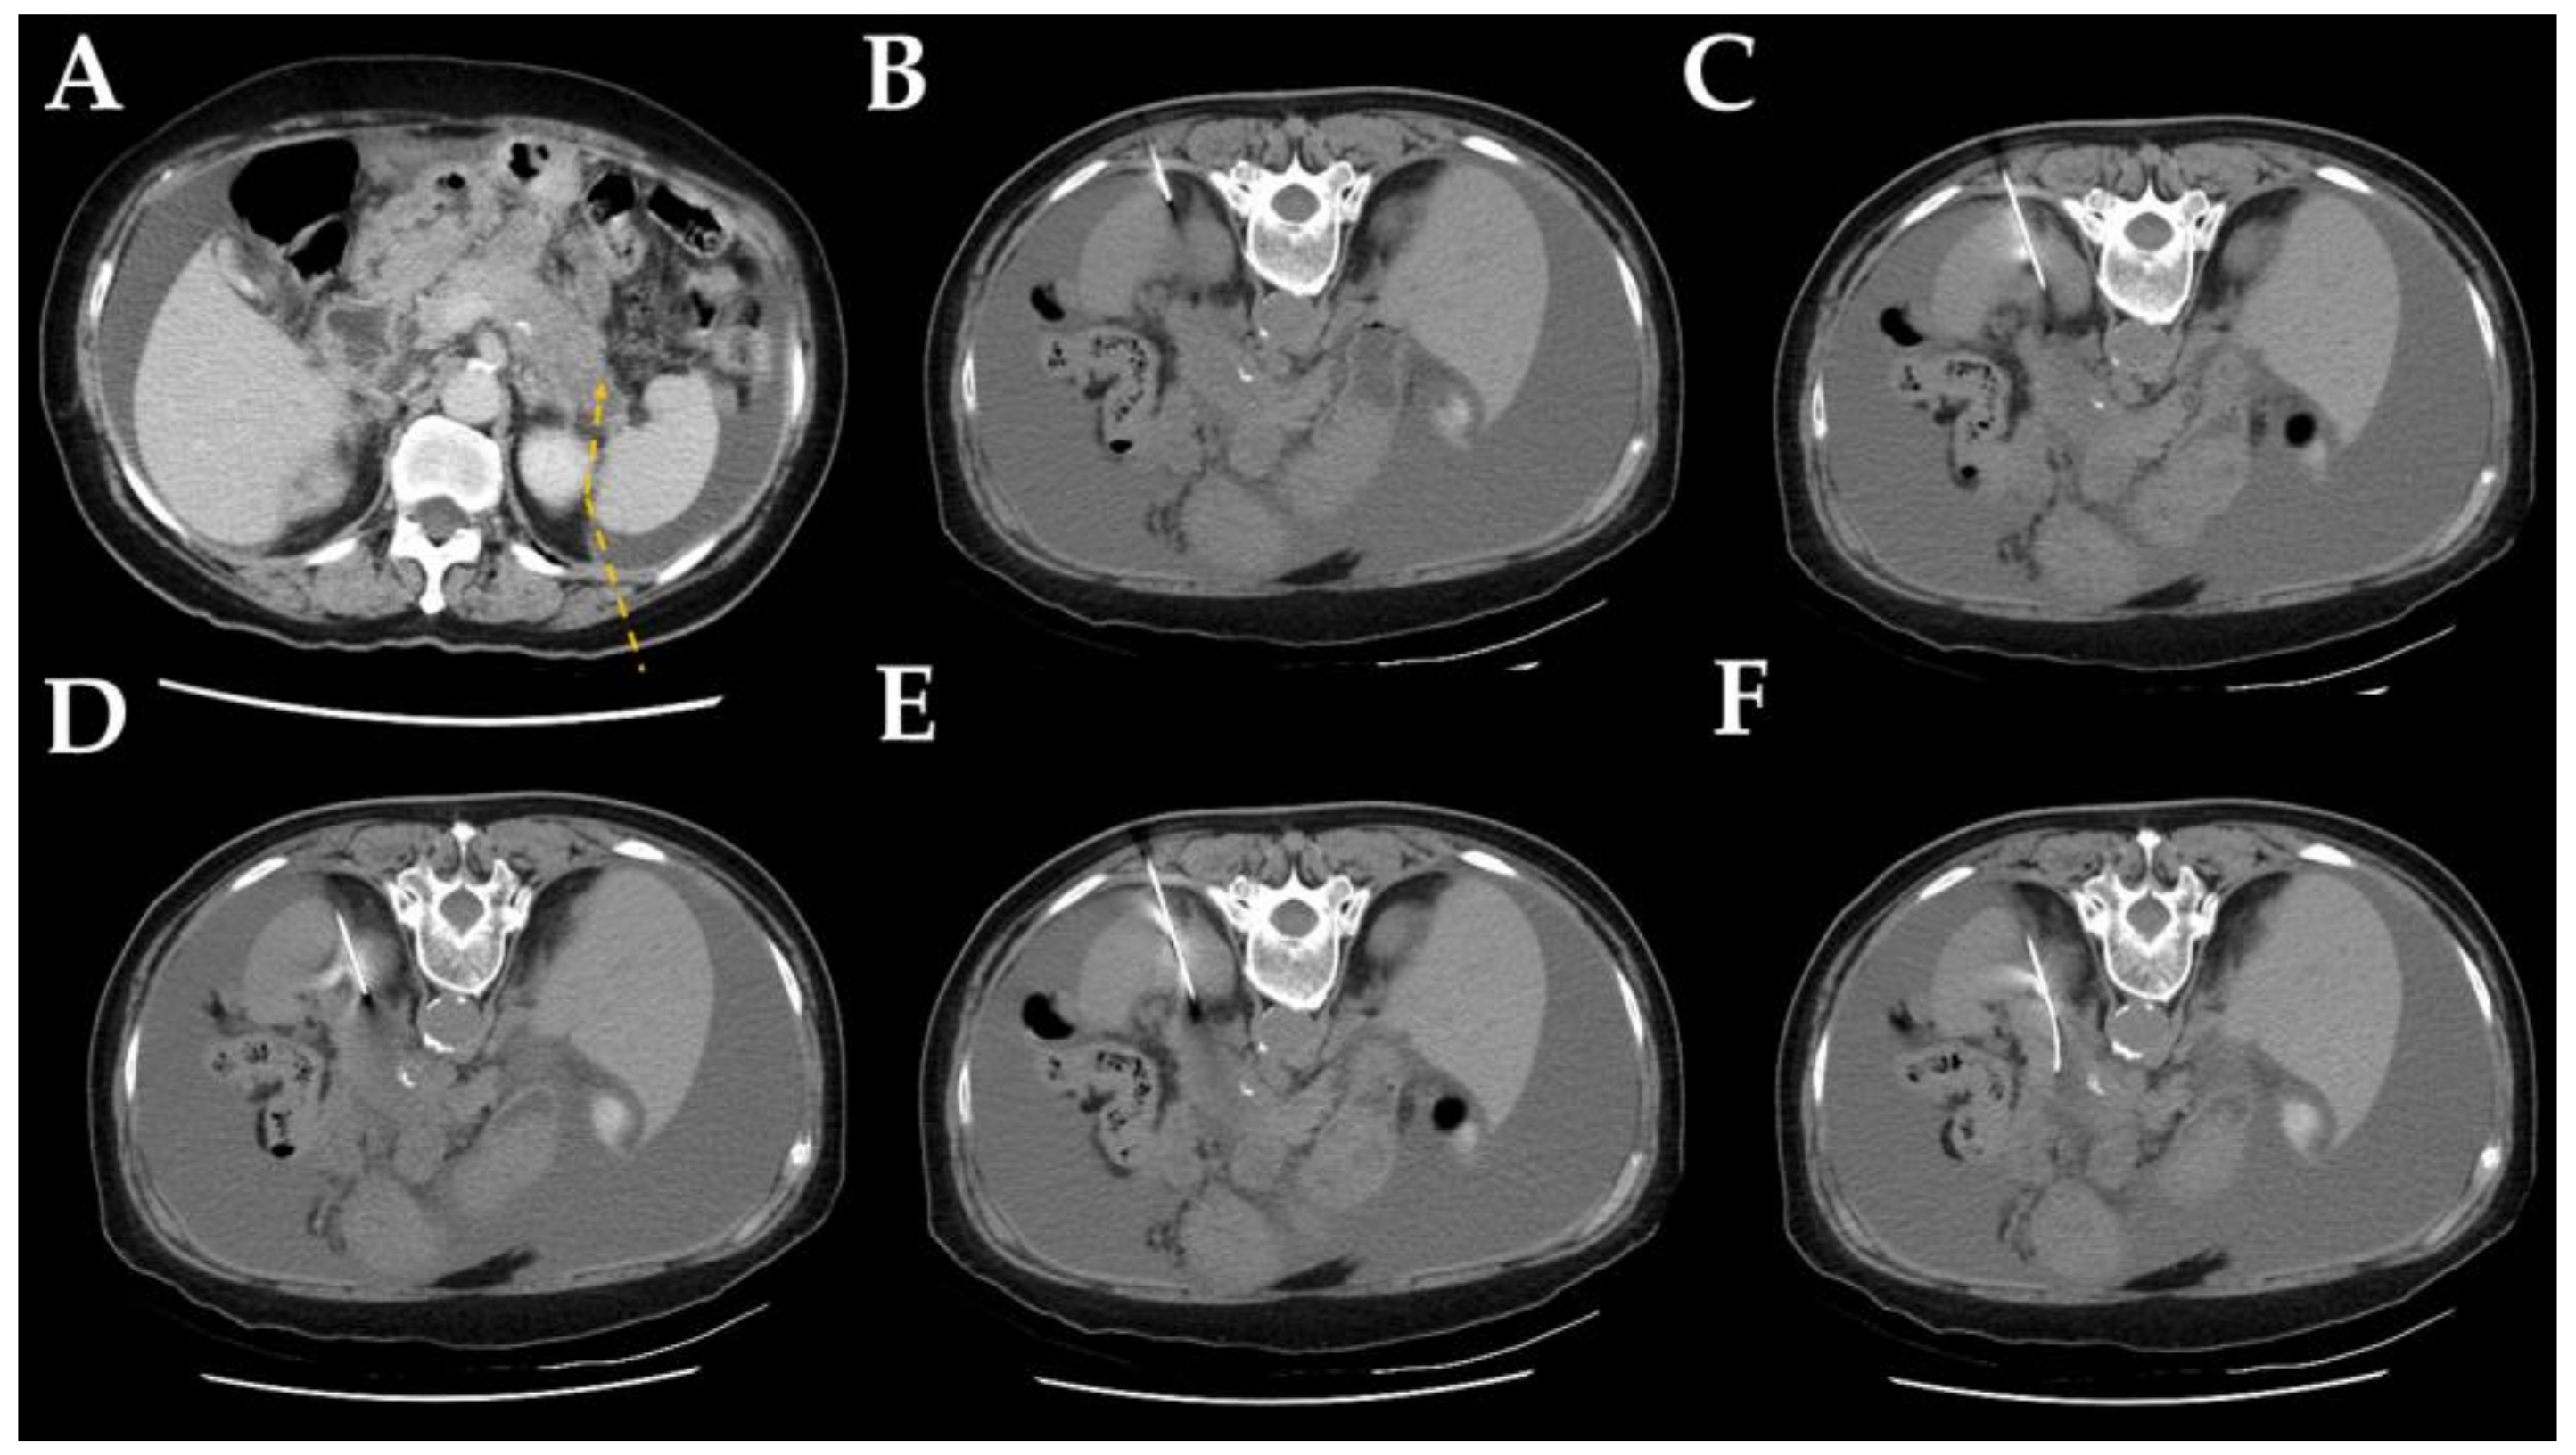

2.2. Computed Tomography-Guided Core Needle Biopsy Technique

| Detour route 1 | 169 | 29 (14–54) |

| Detour route 2 | 169 | 28 (12–51) |

| Detour route 3 | 26 | 28.5 (17–42) |

| Detour route 4 | 19 | 29 (16–41) |

| Detour route 5 | 26 | 29.5 (19–40) |

| Detour route 6 | 11 | 28 (19–38) |

| Detour route 1 | 26 | 49 | 43 | 51 | 169 (40.2%) |

| Detour route 2 | 16 | 32 | 39 | 82 | 169 (40.2%) |

| Detour route 3 | 2 | 4 | 3 | 17 | 26 (6.2%) |

| Detour route 4 | 0 | 2 | 6 | 11 | 19 (4.5%) |

| Detour route 5 | 3 | 10 | 6 | 7 | 26 (6.2%) |

| Detour route 6 | 0 | 6 | 2 | 3 | 11 (2.6%) |